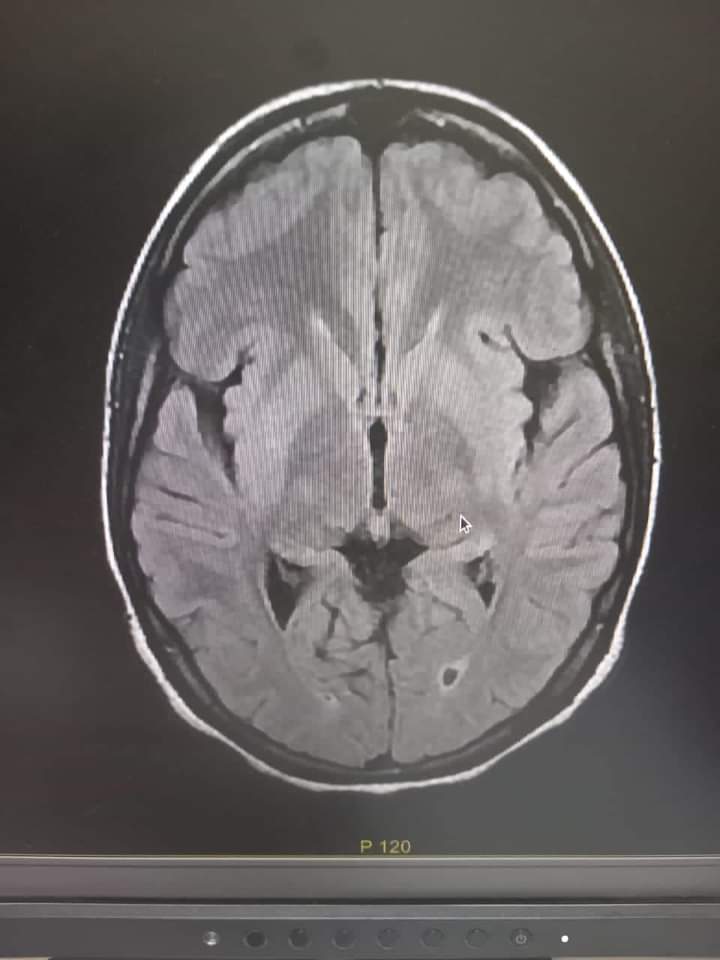

تمكن فريق طبي متخصص بالمستشفى العسكري بنواكشوط، من تفتيت جلطة دماغية لمريضة في العشرينيات من العمر، بعد وصولها في حالة سكتة دماغية منتصف يوم الجمعة للحالات المستعجلة للمستشفى العسكري بنواكشوط.

ووفق المستشفى، قد تمكن الفريق الطبي من تشخيص السكتة الدماغية قبل تجاوز الفترة الزمنية الضرورية (أربع ساعات ونصف)، وقام بتفعيل الإجراءات اللازمة للعلاج، الأمر الذي مكن من الحصول على الدواء الخاص لمثل هذه الحالات واستخدامه.

وأشار المستشفى، إلى أن هذه هي المرة الأولى التي يتم فيها هذا النوع من العلاج، المتقدم و الحديث للسكتات الدماغية في المستشفيات الوطنية، حيث يمكن هذا العلاج المرضى من استعادة وظائفهم الحركية والكلامية، التي عادة ما يفقدونها بشكل نهائي في غياب العلاج.